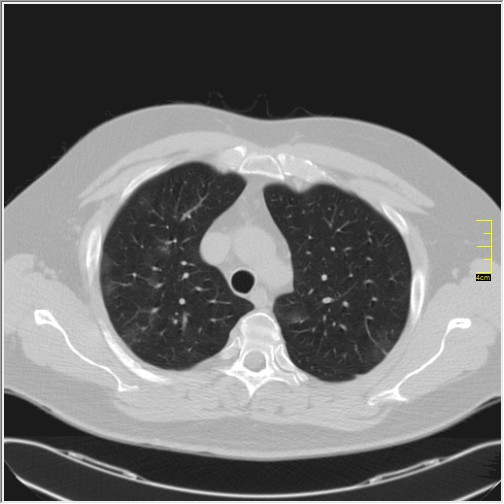

Četiri dana kasnije. Isti pacijent dolazi sa istim pulmologom. Situacija je sada sasvim drugačija. Temperatura 39.5 C. Saturacija 92. Laboratorija daleko gora. Uradim CT pluća. Ovo je izašlo.

Severity score 15/25. Pacijent je upućen na bolničko lečenje.

Ono što zbunjuje, a to se ponavlja zadnjih 10 dana, je da fibroza nastupa u progresivnoj fazi, znači na početku bolesti. Toga nije bilo do sada. Sledećih dana ću o tome.

Ovo je samo 4 dana. Od zdravlja do teške bolesti. Pacijent je 45 godina starosti, očigledno nije povećane težine, kaže za sebe da je bio sportista. U anamnezi nije naveo nikakve bitne bolesti.